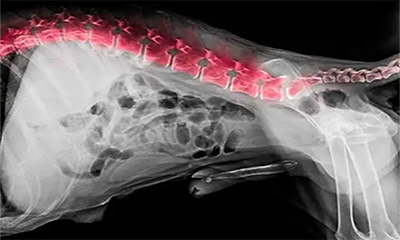

EXAMES

RADIOLOGISTA

Dr. Ms. Jonathan Nantes

CRMV: 0720 SE